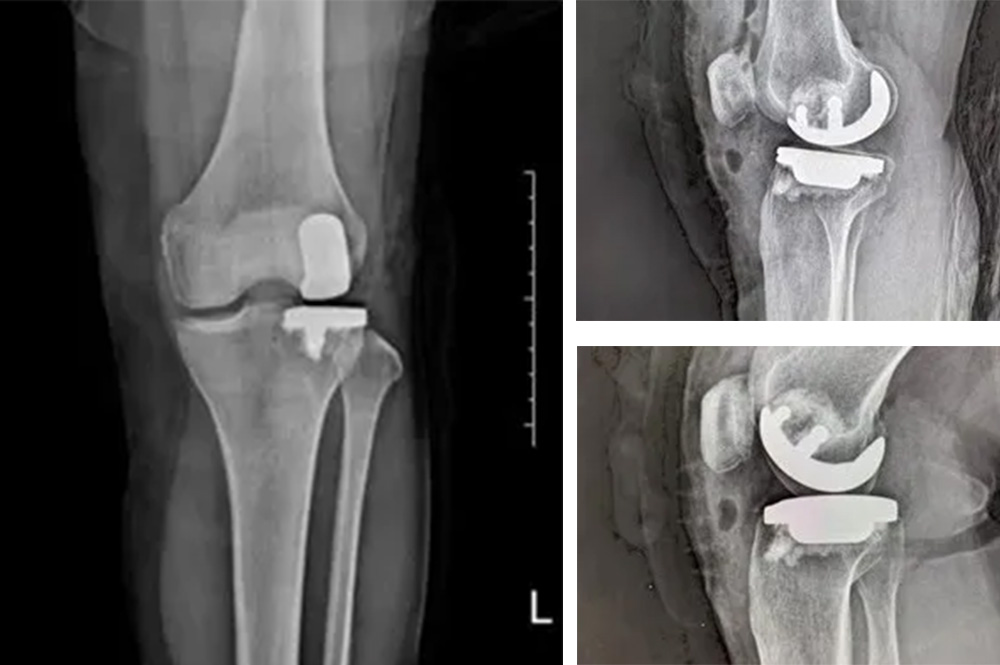

我院骨科主任羅醫(yī)生介紹,膝關(guān)節(jié)分為內(nèi)側(cè)、外側(cè)和髕股三個(gè)間室。鮑奶奶的問(wèn)題主要集中在膝關(guān)節(jié)外側(cè)間室,而內(nèi)側(cè)和髕股關(guān)節(jié)相對(duì)完好。

“傳統(tǒng)全膝關(guān)節(jié)置換會(huì)切除所有關(guān)節(jié)面,而單髁置換只替換病變的部分,保留了健康的韌帶和軟骨,更符合‘精準(zhǔn)醫(yī)療’理念。”羅醫(yī)生說(shuō)。

經(jīng)過(guò)詳細(xì)的體格檢查、影像學(xué)評(píng)估和三維重建,醫(yī)療團(tuán)隊(duì)確認(rèn)鮑奶奶的情況非常適合進(jìn)行膝外側(cè)單髁置換術(shù)。這種微創(chuàng)手術(shù)創(chuàng)傷小、恢復(fù)快,能夠最大程度保留膝關(guān)節(jié)的自然結(jié)構(gòu)和功能。

手術(shù)當(dāng)天,骨科團(tuán)隊(duì)采用微創(chuàng)切口,僅約8厘米,遠(yuǎn)小于傳統(tǒng)全膝關(guān)節(jié)置換手術(shù)切口。術(shù)中精準(zhǔn)定位,僅置換病變的膝關(guān)節(jié)外側(cè)間室。

手術(shù)使用了最新的單髁假體系統(tǒng),這種假體設(shè)計(jì)更符合人體工程學(xué),能夠更好地恢復(fù)膝關(guān)節(jié)的自然運(yùn)動(dòng)軌跡。

膝外側(cè)單髁置換術(shù)是膝關(guān)節(jié)置換領(lǐng)域的重要進(jìn)展。與全膝關(guān)節(jié)置換相比,它具有明顯優(yōu)勢(shì):手術(shù)創(chuàng)傷小,僅置換病變部分;保留更多自然結(jié)構(gòu)和韌帶;術(shù)后恢復(fù)快,住院時(shí)間短;術(shù)后膝關(guān)節(jié)感覺(jué)更自然,活動(dòng)度更好。